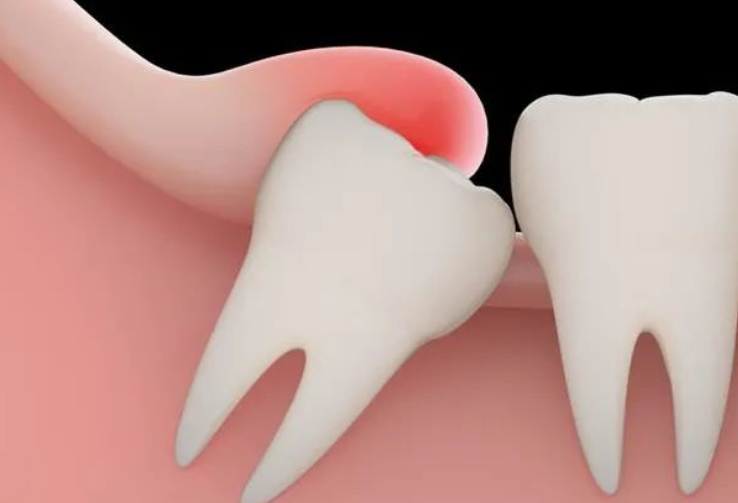

1、拔阻生智齒:拔智齒是這家醫(yī)院很不錯(cuò)的項(xiàng)目之一,醫(yī)生在做阻生和埋伏智齒拔除的時(shí)候,手法都比較細(xì)膩,形成的創(chuàng)口比較小,術(shù)后恢復(fù)的會(huì)比較快。